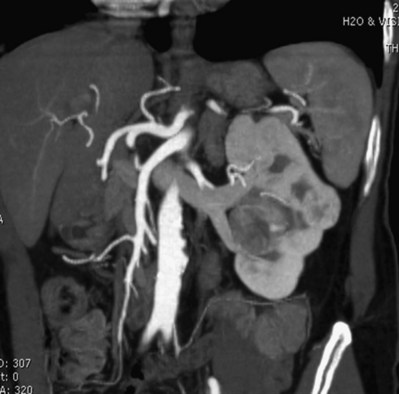

Before partial nephrectomy, evaluation of patients with renal cortical tumors should include imaging to identify locally extensive or metastatic disease. Preoperative imaging should also delineate relevant regional anatomy, intrarenal anatomy, and vasculature to minimize blood loss and damage to adjacent renal parenchyma. Invasive renal arteriography has largely been replaced by noninvasive 3D CT angiography, which offers excellent anatomic detail. 3D CT integrates information from arteriography, venography, excretory urography, and conventional two-dimensional CT into a single imaging modality (Fig. 54–130). In addition to tumor staging, 3D reconstructions of contrast-enhanced CT angiograms, MR images, or MR venograms are useful for planning site and extent of planned resection and to determine proximity to the renal hilum, intrarenal vasculature, and collecting system (Fig. 54–131). 3D CT accurately demonstrates involvement of the collecting system by tumor (Derweesh et al, 2003).

Figure 54–131 A, Contrast-enhanced CT scan demonstrating right renal mass. B, Three-dimensional reconstruction demonstrates a large intrarenal component to the mass. C, Arterial reconstruction shows lower pole renal artery in close proximity to the renal mass.